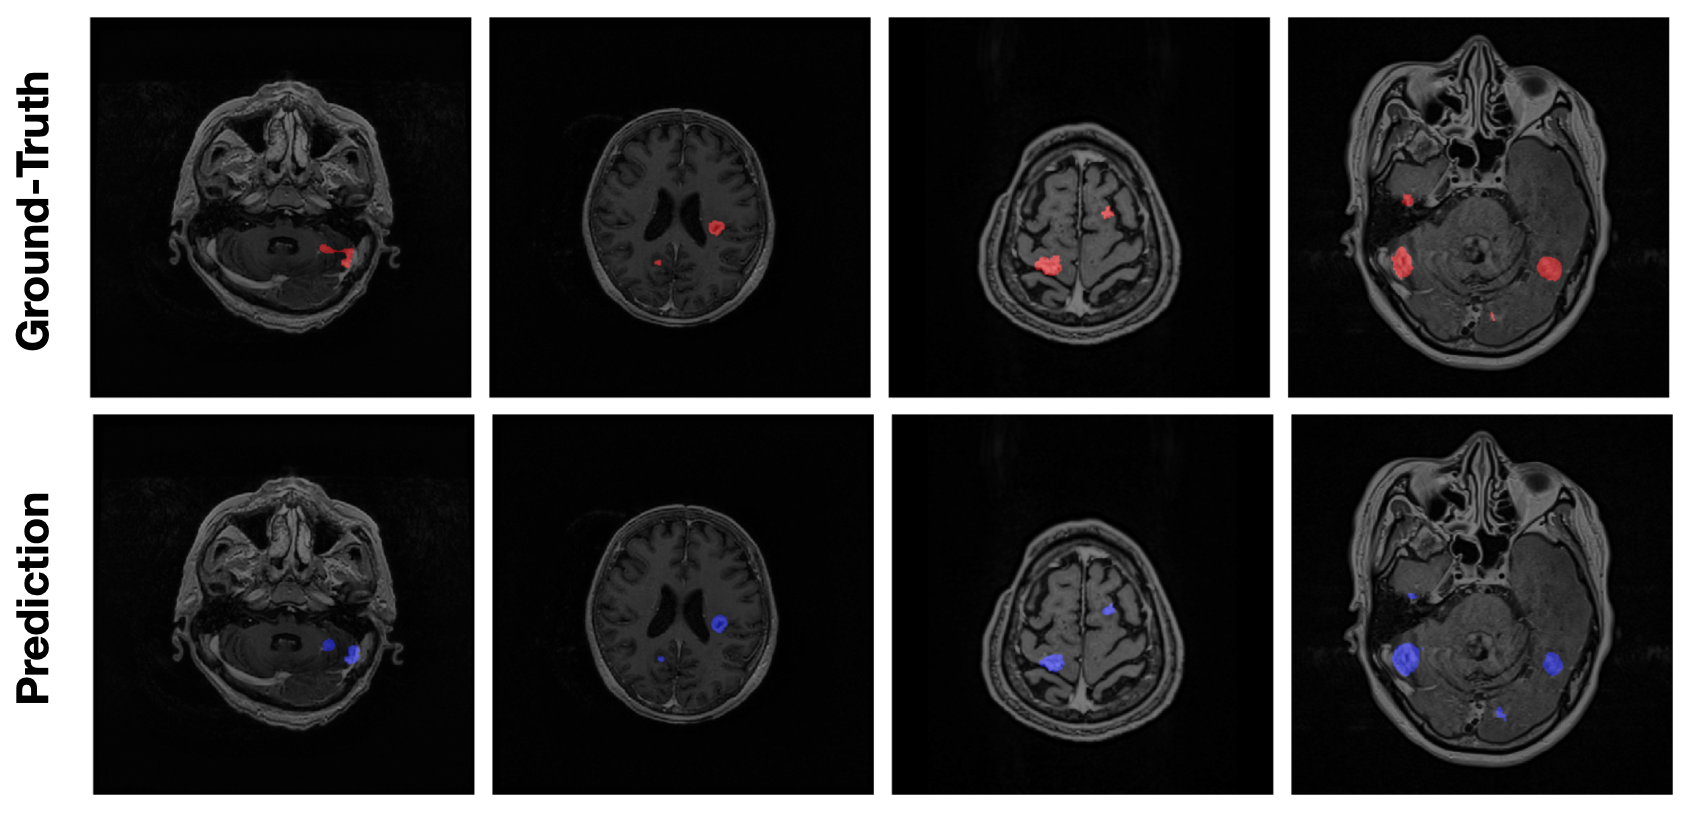

As shown in Table 3, 3D U-Net and DeepMedic obtain a DSC of 0.669 and 0.625 respectively. DeepMedic utilizes a patch-based training method, which makes the network focusing on smaller regions and contributing to a higher recall; on the other hand, 3D U-Net takes full resolution as inputs. The advantage of seeing the complete brain structure leads to higher precision. The ensemble of the two models improves the DSC to 0.719. Further applying the vol-dicesubscriptvol-dice\ell_{\text{\sf vol-dice}} (with BR) on 3D U-Net, we achieve the best DSC of 0.740 and recall of 0.803. The results indicate that our deep learning approach effectively increases the DSC, precision, and recall. The performance surpasses the current benchmark methods. Examples of prediction results are shown in Figure 2.

Refer to caption

Figure 2: Examples of the prediction results overlaying with MRI.